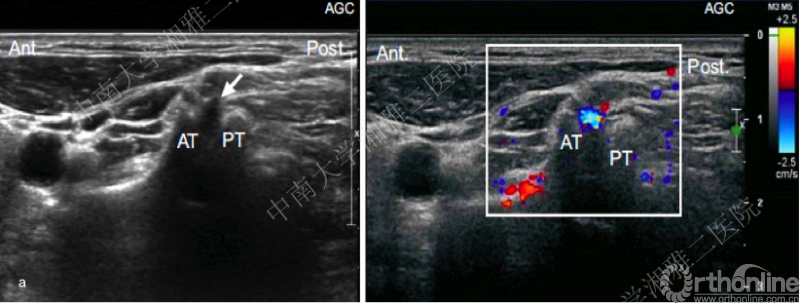

SCNRB超声引导技术

鉴于X线、CT引导在SCNRB技术中的应用局限,近年来,有学者倡导在超声引导下进行SCNRB。在超声对椎间孔周围血管扫描观察研究中[18]显示无论是在C5节段(图a),还是在C6节段(图b),实时多普勒模式下可以清晰辨别椎间孔神经根周围的细小动脉血管,按照表1的统计结果我们可以更好的发现,在传统的穿刺路径上越是颈椎低节段穿刺,穿刺针误入小动脉血管的风险越高。因此超声引导SCNRB可能具有的优势在于:1.无辐射 2.有效避免小动脉血管损伤[19]。

图a